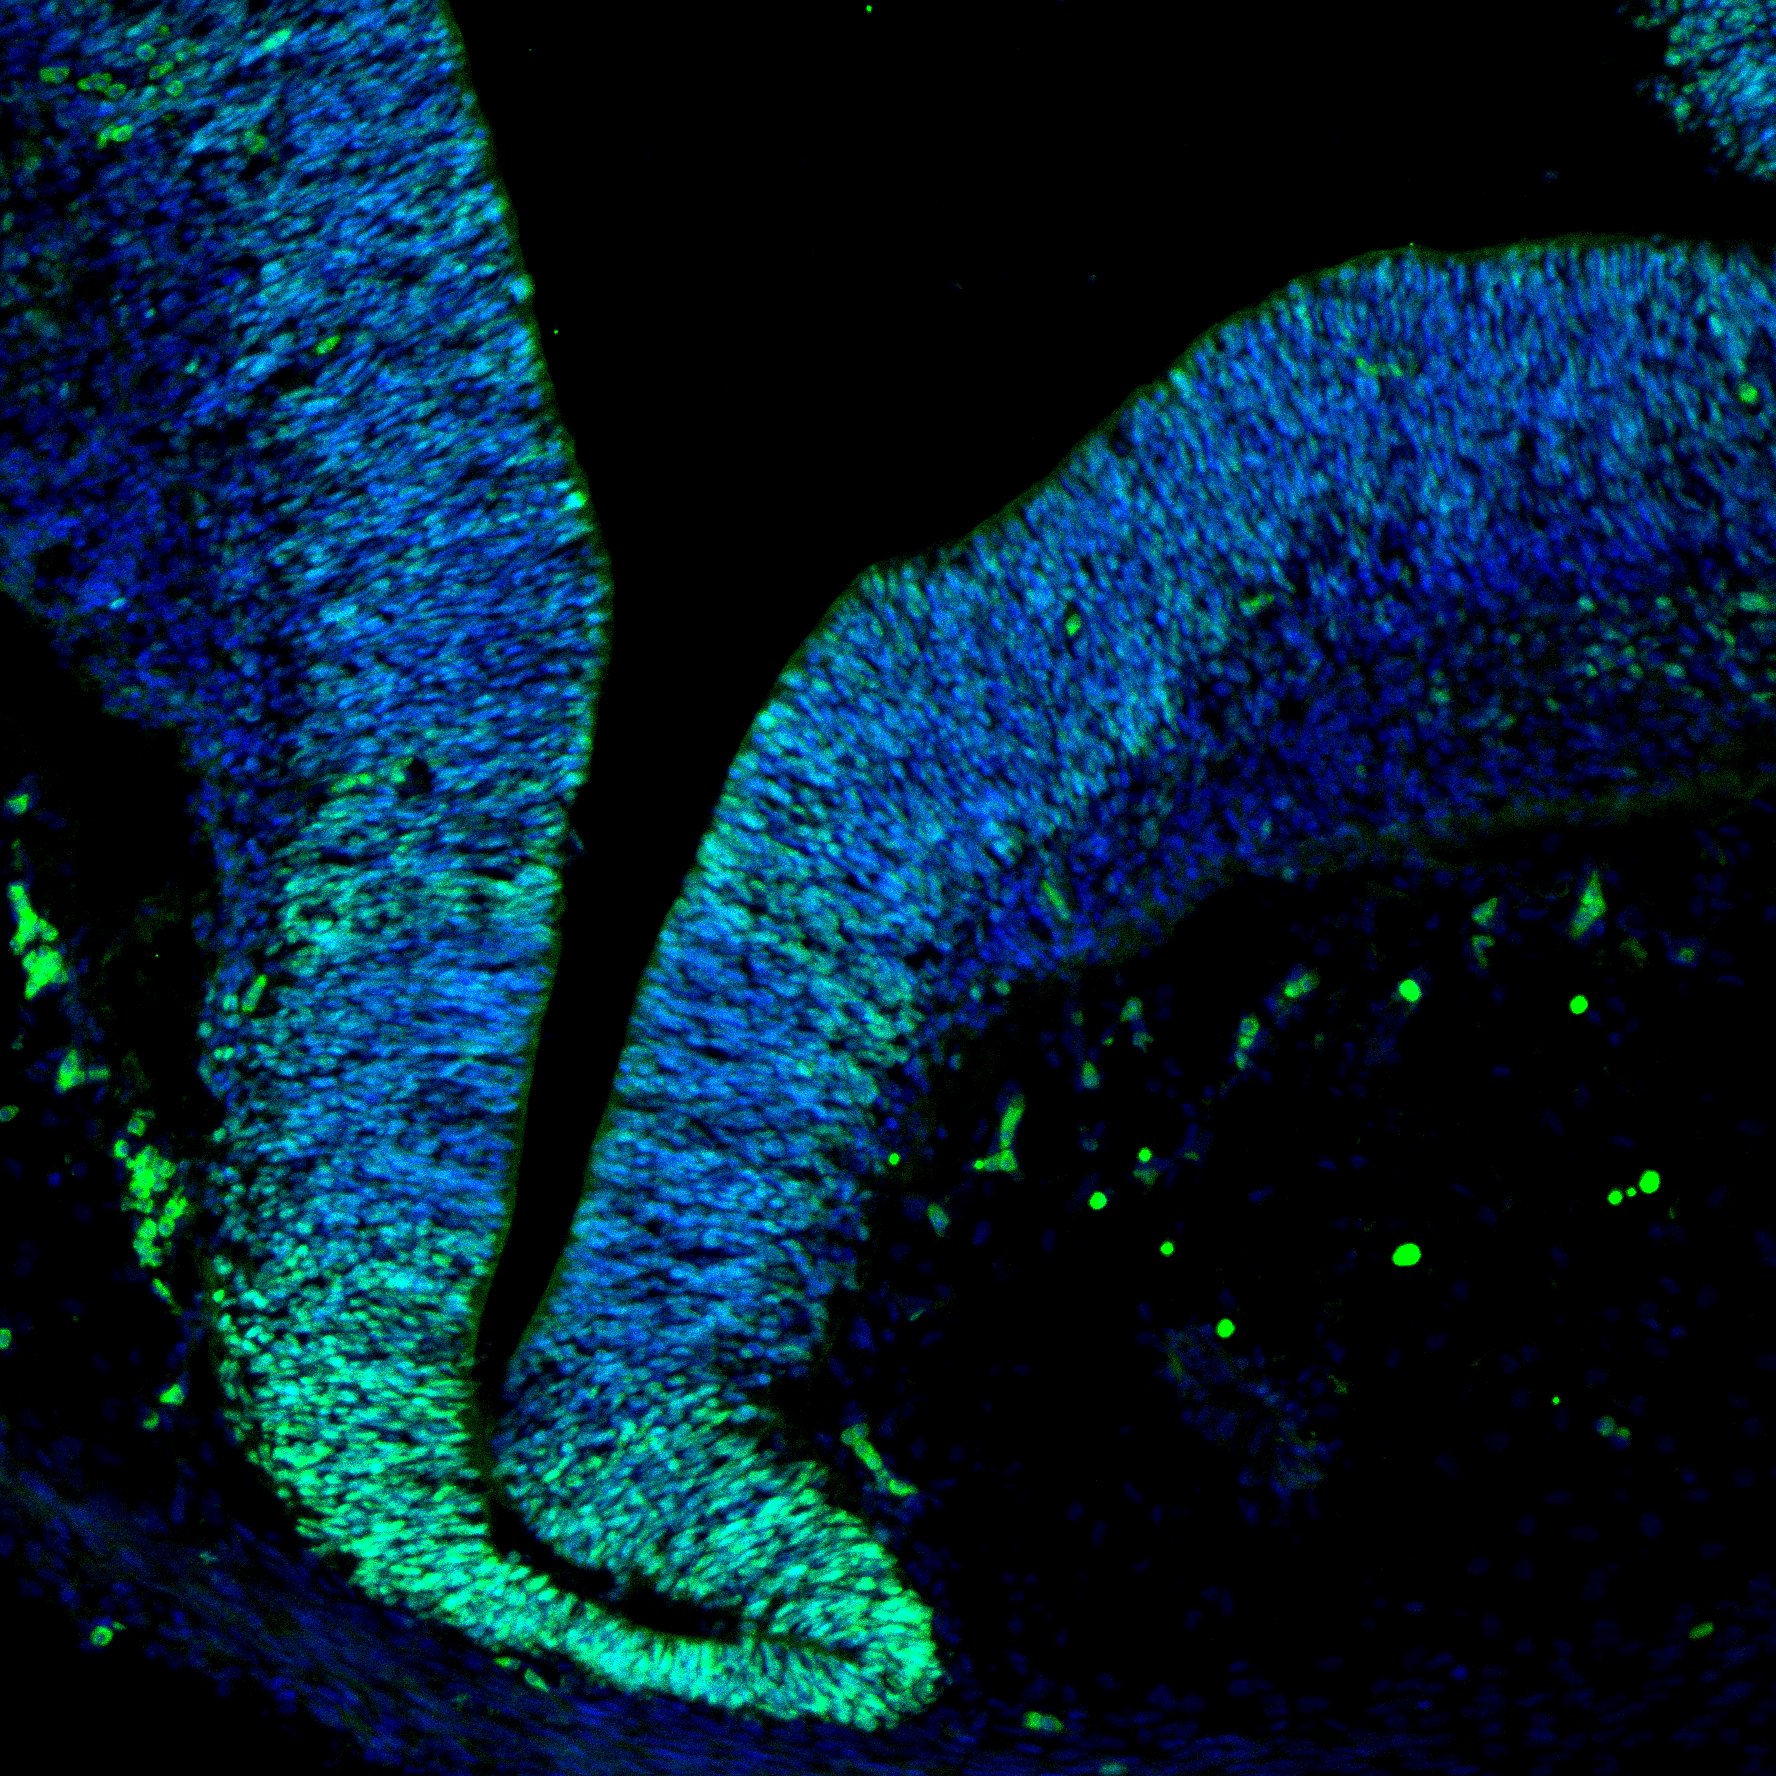

An anatomical analysis of the developing human midbrain from 6 post-conceptional weeks (PCW) to 22 PCW reveals increased tissue complexity, characterized by the emergence of dopaminergic nuclei, as highlighted by immunofluorescence analysis for tyrosine hydroxylase (TH).

DAPI

7PCW human midbrain

MAP2

TH

Merged